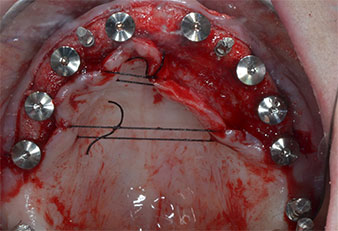

Пиезоелектрически инструмент с диамантено покритие с форма на пламък (Piezomed I1) e използван за маркиране на позициите на имплантите и за пилотна подготовка (Фиг. 3). Препарацията беше извършена с внимателни вертикални движения, с намалена мощност, пълна иригация и лек натиск (под 300 g) След това се приложи пилотен инструмент (Piezomed I2A/ I2P) за първоначално увеличение на диаметъра на имплантното ложе с 2 mm (Фиг. 4), последвано от 3 mm разширение (Фиг. 5)

В случай на твърда кост, цялата поредица от инструменти, включително междинните инструменти Piezomed Z25P и Z35P, трябва да се използват за разширяване на остеотомиите.

Те също така са предназначени за подготовка в близост до синусовата мембрана във връзка с вътрешни аугметационни процедури или когато има по-малко от 4 mm остатъчна височина на костта.

В настоящия случай инструменти Z25P и Z35P не са използвани поради сравнително меката задна кост, която лесно се обработва с I3A/I3P.

Поради сравнително твърдата кост (D2) в тази област, 10-милиметровото имплантно ложе в позиции 11 и 21 беше завършено с ротационен дрил с диаметър 4 mm в комбинация с W&H хирургичен обратен наконечник WS-75 L, W&H имплантологичен мотор Implantmed и опционалния W&H Osstell ISQ модул. За разлика от това, благодарение на меката кост, дисталните зони се подготвят до окончателен диаметър 3 mm, използвайки накрайник за Piezomed I3P. Имплантите най-накрая са поставени трансгингивално, за да остеоинтегрират за три месеца (Фиг. 6-10). Съществуващата протеза се фиксира на четирите временни импланта (Фиг. 8).